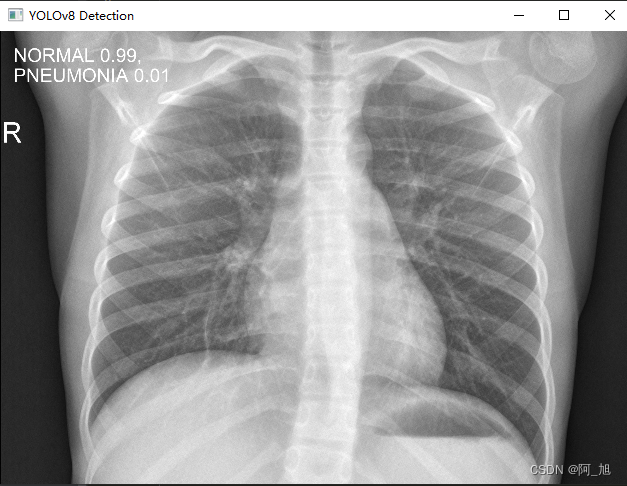

执行上述代码后,会将执行的结果直接标注在图片上,结果如下: